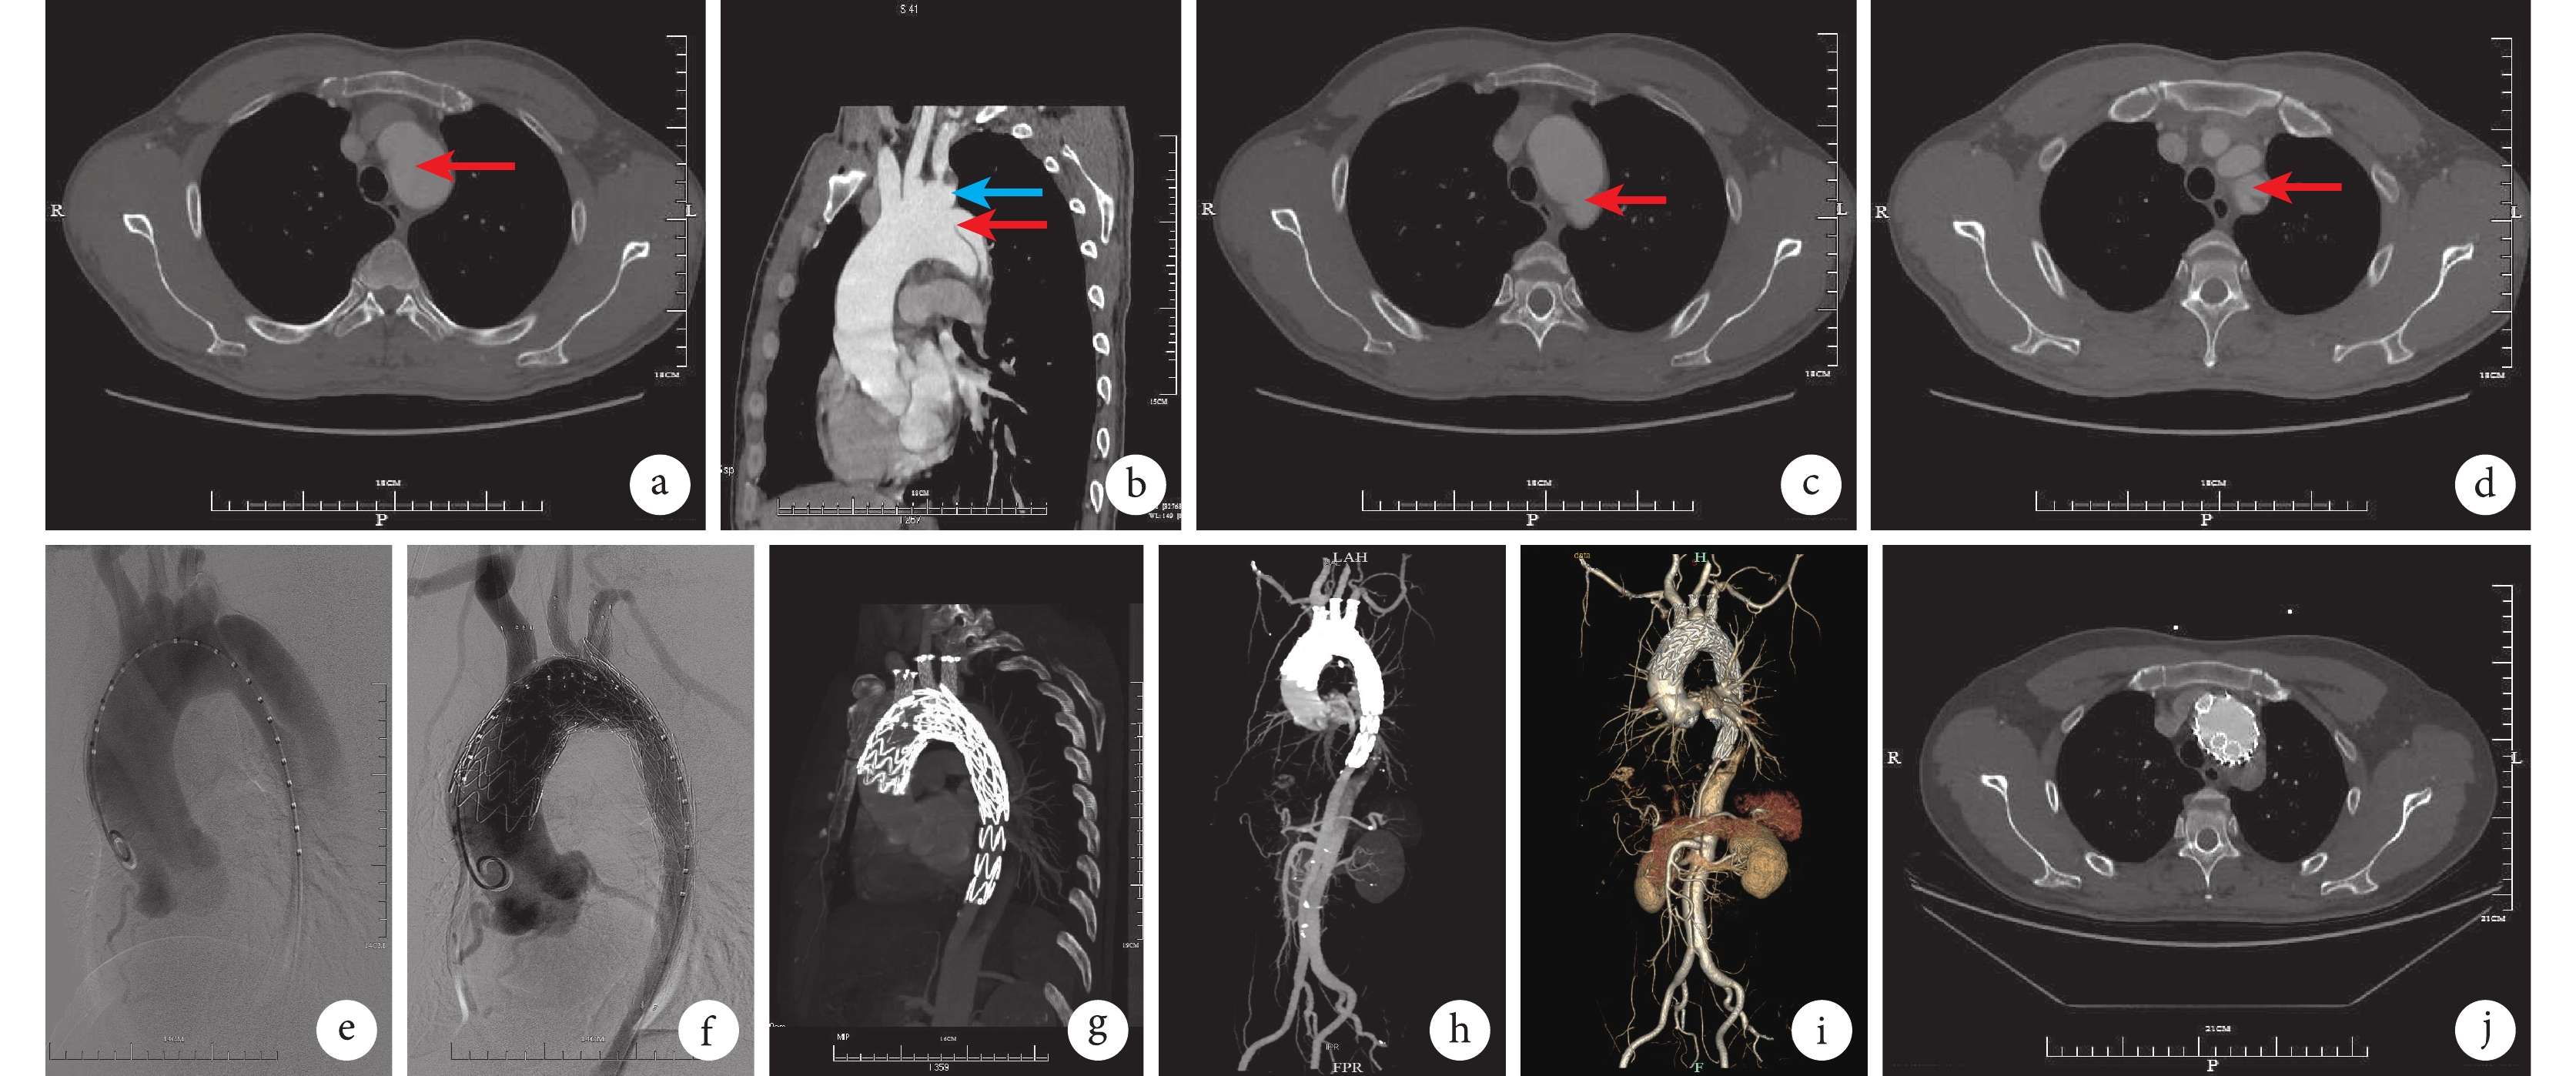

a~d:為手術前主動脈CTA檢查,a圖見主動脈弓部瘤(紅箭),b圖見弓部瘤(藍箭)合并B型夾層(紅箭),c圖見破口位于鎖骨下動脈根部(紅箭),d圖見左鎖骨下動脈受累(紅箭);e:造影顯示主動脈弓部瘤合并B型主動脈夾層,破口位于左鎖骨下動脈根部,左鎖骨下動脈受累; f:術后造影顯示主動脈弓部瘤及夾層隔絕,支架形態良好,無內漏,左右冠狀動脈顯影良好,3個分支顯影良好; g~i: 分別為術后3(g)、 6(h)和12(i)個月復查CTA ,見支架主體及3個分支通暢、在位、無內漏發生; j:為術后12個月復查CTA斷層,見支架主體及3個分支通暢、無內漏發生

患者男性,41歲,以“胸背部撕裂樣疼痛2 h”為主訴于2020年1月19日收住河西學院附屬張掖人民醫院血管外科。患者既往有高血壓病史多年且未正規治療及監測血壓,血壓最高達210/150 mmHg(1 mmHg=0.133 kPa)。無糖尿病、冠心病等其他病史。入院時患者血壓為200/120 mmHg。行主動脈全程CT血管造影(computed tomography angiography,CTA)檢查,提示主動脈弓部瘤樣改變,主動脈夾層(Stanford B型),左鎖骨下動脈累及(圖1a~1d),腹腔干、腸系膜上動脈騎跨真假腔,腹腔干近段狹窄;左腎動脈開口于假腔。診斷:主動脈弓部動脈瘤、主動脈夾層Stanford B型 高血壓病3級(很高危組)。

患者入院后即給予降壓、控制心率、鎮痛等對癥處理,并于入院后1周在氣管插管全身麻醉下行腔內治療聯合體內原位開窗3個分支重建術。 具體手術步驟為 ① 準備:于左側鎖骨上窩取橫行切口約4 cm長,左、右側頸部縱行切口約3 cm長,右側腹股溝斜行切口約4 cm長,顯露雙側頸總動脈、左鎖骨下動脈及右側股動脈,分別繞以阻斷帶,5-0 Proline血管縫線于雙側頸總動脈、左鎖骨下動脈及右側股動脈做荷包備用。全身肝素化后,于雙側頸總動脈逆行、順行分別置入10F血管鞘,左鎖骨下動脈逆行置入10F血管鞘,右側股動脈逆行置入24F親水涂層導引鞘(戈爾)。② 造影:經右側股動脈血管鞘沿真腔送入超滑泥鰍導絲、5F豬尾巴導管至升主動脈行造影檢查,結果提示主動脈弓部瘤并B型主動脈夾層(破口位于左鎖骨下動脈根部),見圖1e。③ 釋放主體:主動脈主體近端覆膜支架選擇C-TAG(美國Gore,40-40-200),遠端續接Hercules(上海微創心脈科技,32-28-160),經右側股動脈入路送至預定位置釋放;迅速造影顯示主動脈弓部瘤及夾層隔絕,頭臂干、左頸總動脈及左鎖骨下動脈封閉;撤出輸送系統及導絲導管。④ 腦保護:于右側股動脈24F鞘內置入2根10F血管鞘,分別連接轉流管接入雙側頸動脈順行血管鞘行股-雙側頸動脈外轉流。⑤ 體內原位開窗:頭臂干,經右側頸動脈逆行血管鞘進入穿側套筒裝置至支架主體,不同角度旋轉C臂確認套筒口位置在弓頂,確認穿刺點,進入穿刺針穿刺支架主體見有噴血,經穿刺針送入Landerquist導絲至主體支架內,撤出穿刺針進入球囊擴張導管(12 mm×40 mm,波科)擴張穿刺孔,撤出球囊后送入覆膜支架FLUENCY(Bard公司,美國,13.5 mm×40 mm)于預定位置釋放。左頸總動脈,采用同法經左頸動脈逆行血管鞘穿刺成功后進入球囊擴張導管(10 mm×40 mm,波科)擴張穿刺孔,撤出球囊后送入覆膜支架FLUENCY(Bard公司,美國,10 mm×40 mm)于預定位置釋放。左鎖骨下動脈,采用同法經左鎖骨下動脈逆行血管鞘穿刺成功后進入球囊擴張導管(8 mm×40 mm,波科)擴張穿刺孔,撤出球囊后送入覆膜支架FLUENCY(Bard公司,美國,12 mm×40 mm)于預定位置釋放,撤出輸送系統及轉流管,再次造影見主動脈弓部瘤及夾層隔絕,無內漏,左右冠狀動脈顯影良好,主動脈形態良好,頭臂干、左頸總動脈及左鎖骨下血管通路顯影良好、無內漏,雙側椎動脈顯影(圖1f)。開窗用時25 min,撤出導絲導管,拔出各血管鞘,收緊荷包閉合各動脈穿刺點,逐層縫合各切口,無菌敷料包扎,術畢。手術順利,麻醉滿意,手術歷時約150 min,術中出血約100 mL,患者清醒后安返病房。術后給予控制血壓、預防感染、雙抗板等對癥治療,恢復順利,1周后出院。術后3、6及12個月復查主動脈CTA未見明顯異常,支架主體及3個分支通暢在位(圖1g~1j)。該患者在繼續隨訪中。